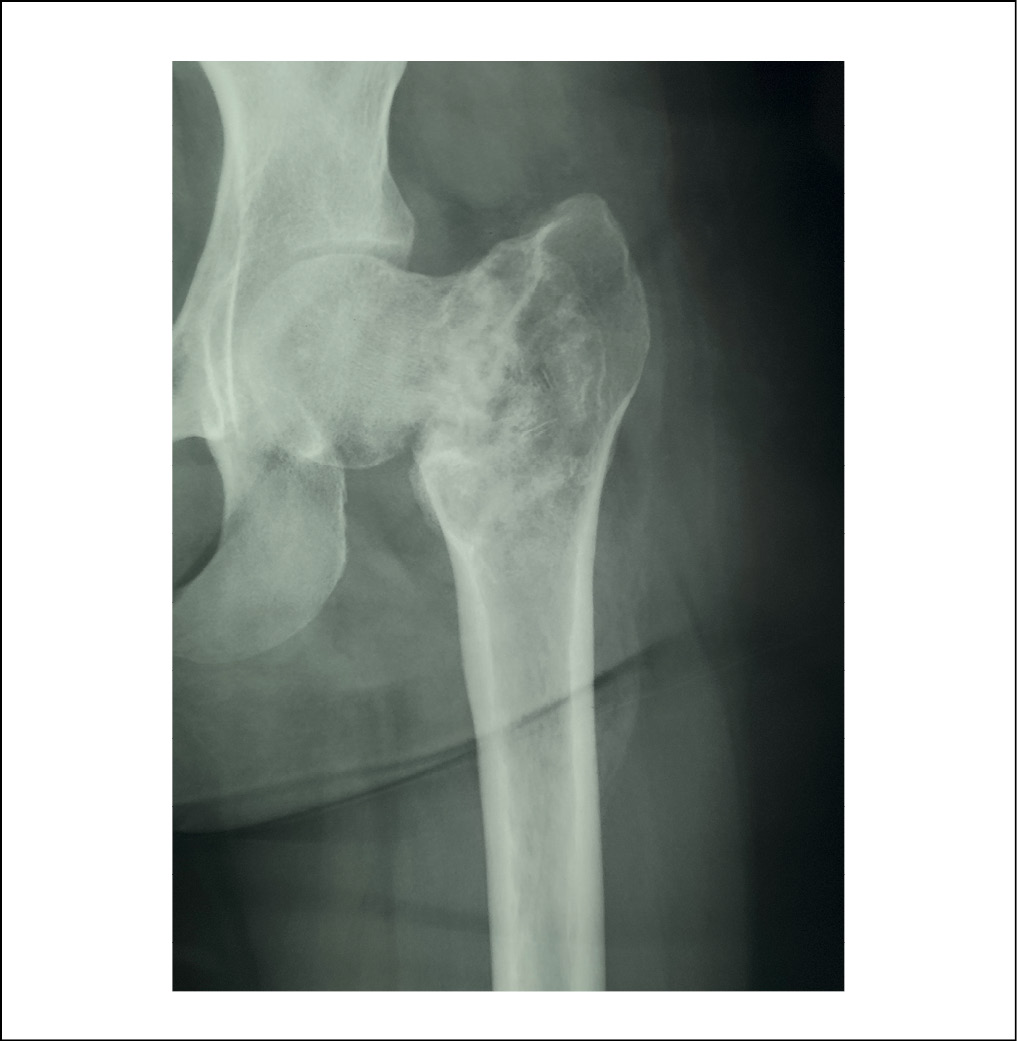

Пациентка K., 2000 г. p., в декабре 2017 года обратилась за консультацией в Клиники Самарского государственного медицинского университета по поводу случайно выявленного в ходе рентгенографии патологического образования проксимального отдела левой бедренной кости (рисунок 1).

Рисунок. 1. Рентгенограмма левого тазобедренного сустава пациентки К., 2000 г.р., в прямой проекции, 2017 г. Отмечаются признаки наличия солитарной костной кисты в проксимальном отделе бедренной кости (границы отмечены стрелками). / Figure 1. X-ray of the left hip joint of patient K., born in 2000, in direct projection, 2017. There are signs of a solitary bone cyst in the proximal femur (the borders are marked with arrows).